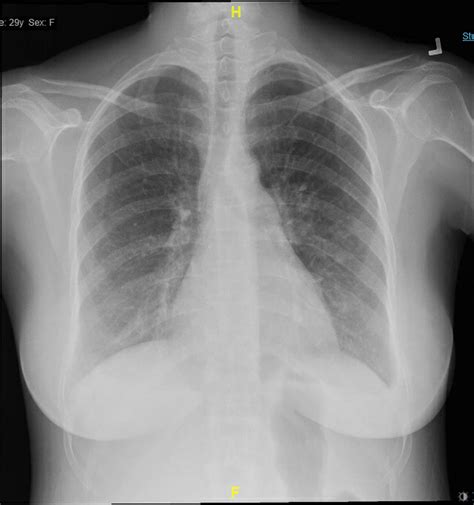

When to Consult a Medical Professional

While most instances of mucus in chest are manageable at home, there are times when professional medical intervention is necessary. You should contact your doctor if the congestion persists for more than a week or if you experience “red flag” symptoms that suggest a more serious bacterial infection or respiratory complication.

Seek medical attention if you notice:

• Difficulty breathing or shortness of breath.

• A fever higher than 101°F (38.3°C) that lasts for more than a few days.

• Chest pain that worsens when coughing or breathing deeply.

• Mucus that is bright red, pink, or dark brown (indicating blood).

• Wheezing that does not go away with home remedies.